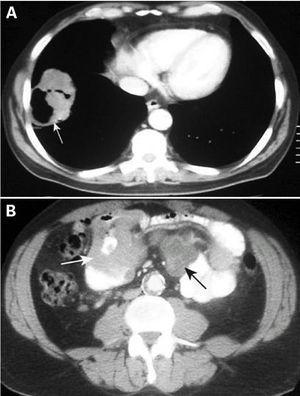

Fig. 2. Imagen de tomografía axial computarizada (TC), con contraste intravenoso, de los lóbulos inferiores(A), donde se observa una masa sólida cavitada en el lóbulo inferior derecho (flecha blanca). En la imagen de TC con contraste intravenoso de la cavidad abdominal inferior (B), se observan un engrosamiento de asas del intestino delgado (flecha blanca) y adenopa-tías mesentéricas (flecha negra), hallazgos en relación con metástasis de un carcinoma primitivo de pulmón de células grandes indiferenciado.